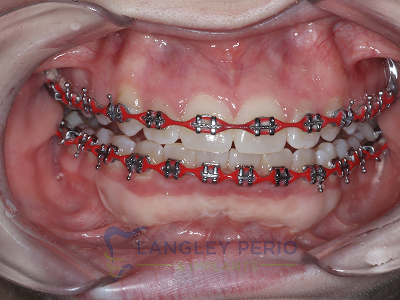

Case 2

Connective tissue grafting was done to cover exposed root surfaces to help to prevent root cavities from developing and reduce temperature sensitivity.